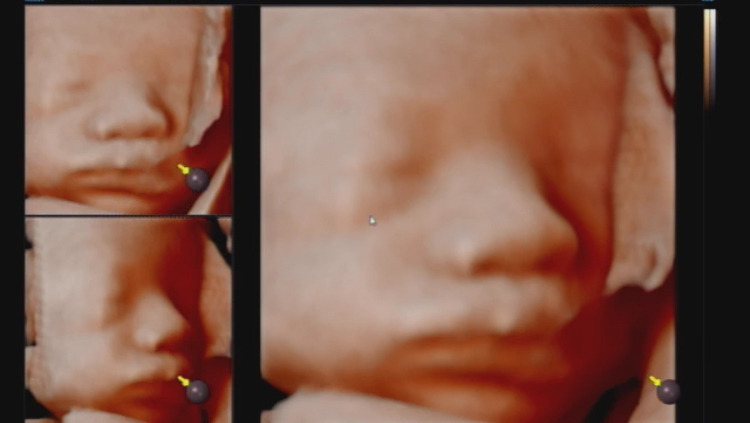

입체초음파 찍는 날이었어요. 임신바우처 체크카드로 61,300원을 지출했죠. 2시 50분까지 가야 하는데 늦어서 부랴부랴 갔더니 뱃속의 모든 장기를 가진 아기가 얼굴을 잘 보여주진 않았어요.

61,800원의 결과물 중 하나. 여기에 살이 더 올라서 나올 거래요. 음 정면이 저렇게 생겼으면 말 다했죠. 뭐. 이젠 2주마다 한 번씩 병원가서 환자로 그렇게 체킹하는 시간을 보내야겠네요.